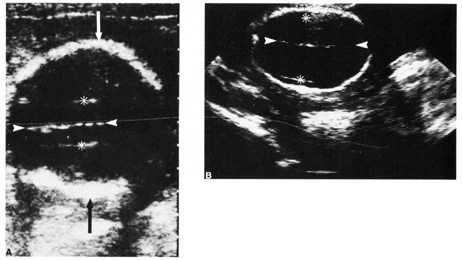

Fig. 6. A: First-trimester twin intrauterine gestations. Ultrasound examination of the pregnant uterus (arrowheads) shows the “owl eyes” characteristic of early twin pregnancies. B: Maternal urinary bladder. (Courtesy of Alfred B. Kurtz, MD)

Fetal number (Fig. 6)